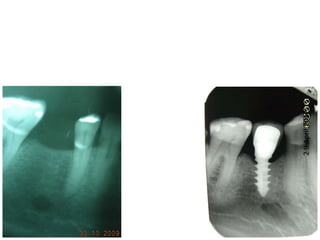

Dogmar Dasgupta,March,2009

Immediately after operation

On 11th.March,2009.

2

9

April,2012